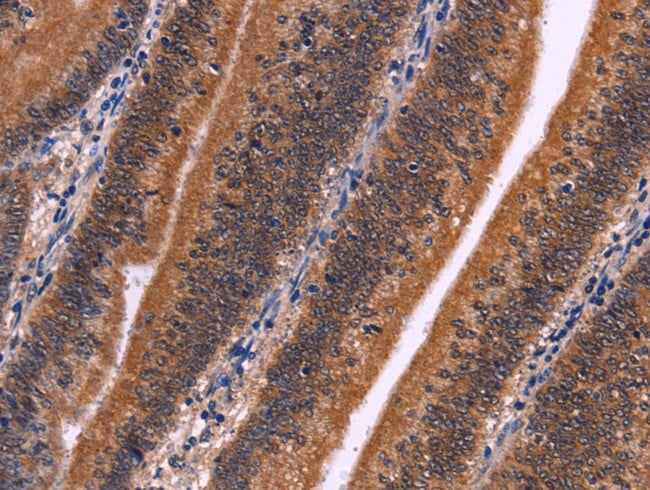

IHC (Immunohistochemistry)

(At 1/100 staining human kidney cancer tissue sections by IHC-P. The tissue was formaldehyde fixed and a heat mediated antigen retrieval step in citrate buffer was performed. The tissue was then blocked and incubated with the antibody for 1.5 hours at 22 degree C. An HRP conjugated goat anti-rabbit antibody was used as the secondary)